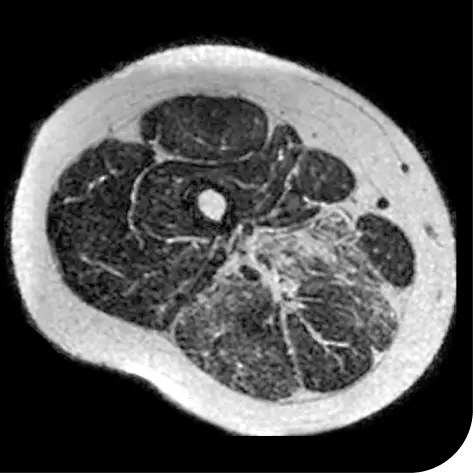

In another follow-up analysis of the clinical trial (meaning it was not one of the main measures planned when the study began), researchers looked at individual people to see how much new fat was in the muscle. The images below represent results from 2 individual people from the study after 18 months. These results may not be the same for everyone.

How to read these images:

- Magnetic resonance spectroscopy (MRS) images can show the difference between muscle and fat in the body

- By taking images of the same patients 18 months apart, researchers can track the amount of new fat that is building up in the muscles

- The darker areas of the images represent muscle tissue and the white areas represent fat

| At the beginning of the clinical trial |

Participant taking DUVYZAT + steroids |